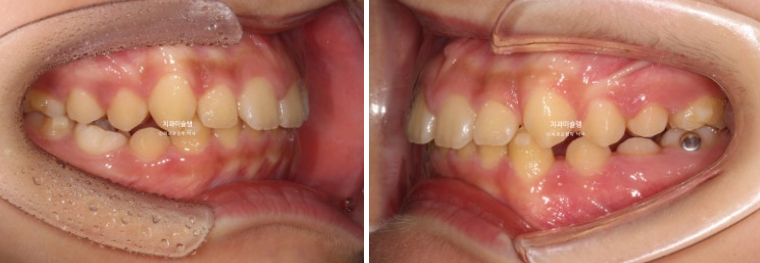

24.10

그 사이 남은 유치들이 정리되고 영구치들이 꽤 나왔습니다. 이제 재제작 타이밍이죠

24년 12월부터 25년 8월까지ㅏ 추가장치를 모두 낀 후 치료를 마무리 했습니다.